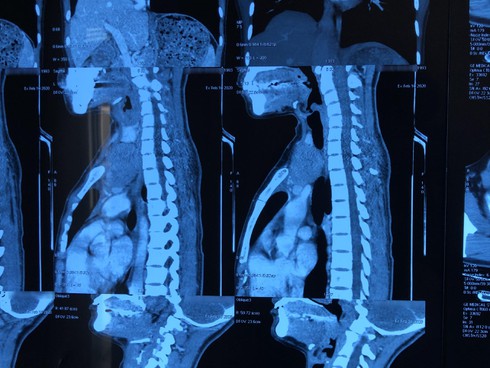

Khối u tuyến ức lạc chỗ lên cổ bệnh nhân trên phim. |

Thấy cổ to lên bất thường, chị N.T.H., sinh năm 1993, trú tại Cẩm Khê, Phú Thọ liền đến Bệnh viện Ung Bướu Hà Nội để kiểm tra. Qua thăm khám ban đầu, nghi ngờ có u giáp trái, bệnh nhân được chỉ định chụp cắt lớp 64 dãy vùng cổ kết hợp sinh thiết kim. Kết quả giải phẫu bệnh và chẩn đoán hình ảnh xác định là u tuyến ức typ AB tại vị trí trung thất trước trên và một phần vùng cổ trái kích thước 8x5cm hay còn gọi là u tuyến ức lạc chỗ.